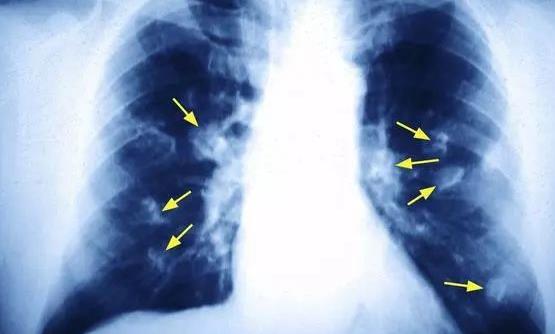

我国国家癌症中心的最新报告显示,肺癌是女性第二高发的癌症,仅次于乳腺癌。40-50岁女性中肺癌患者人数已经接近男性,达到了1:1的比例。但是国内女性的吸烟率很低,为何发生肺癌的概率却如此“不协调”地高呢?下面跟随作文库知识百科了解一下吧!

对肺癌患者长达5年的追踪病因调查发现,70%的男性肺癌患者死于吸烟病因,只有18%的女性患者因吸烟或长期被动吸烟致肺癌。

当然是做饭!调查发现,在不吸烟的女性肺癌患者中,超过60%的女性不仅在家做饭,还在厨房中长期吸入油烟。

在非吸烟女性肺癌危险因素中,超过60%的女性长期接触厨房油烟;有32%的女性烧菜喜欢用高温油煎炸食物,同时厨房门窗关闭,厨房小环境油烟污染严重;25%的女性家中厨房连着卧室,冬天又很少开窗,高温油烟久久不散,甚至睡觉时也在吸油烟!

调查表明,这种病因在中老年女性肺癌患者中特别突出,危险因素达到了正常人的2-3倍。

这是由于厨房做饭时高温油烟产生有毒烟雾,使局部环境恶化,有毒烟雾长期刺激眼和咽喉,损伤呼吸系统细胞组织,如果没有足够的防护措施,就很容易使肺癌发生。